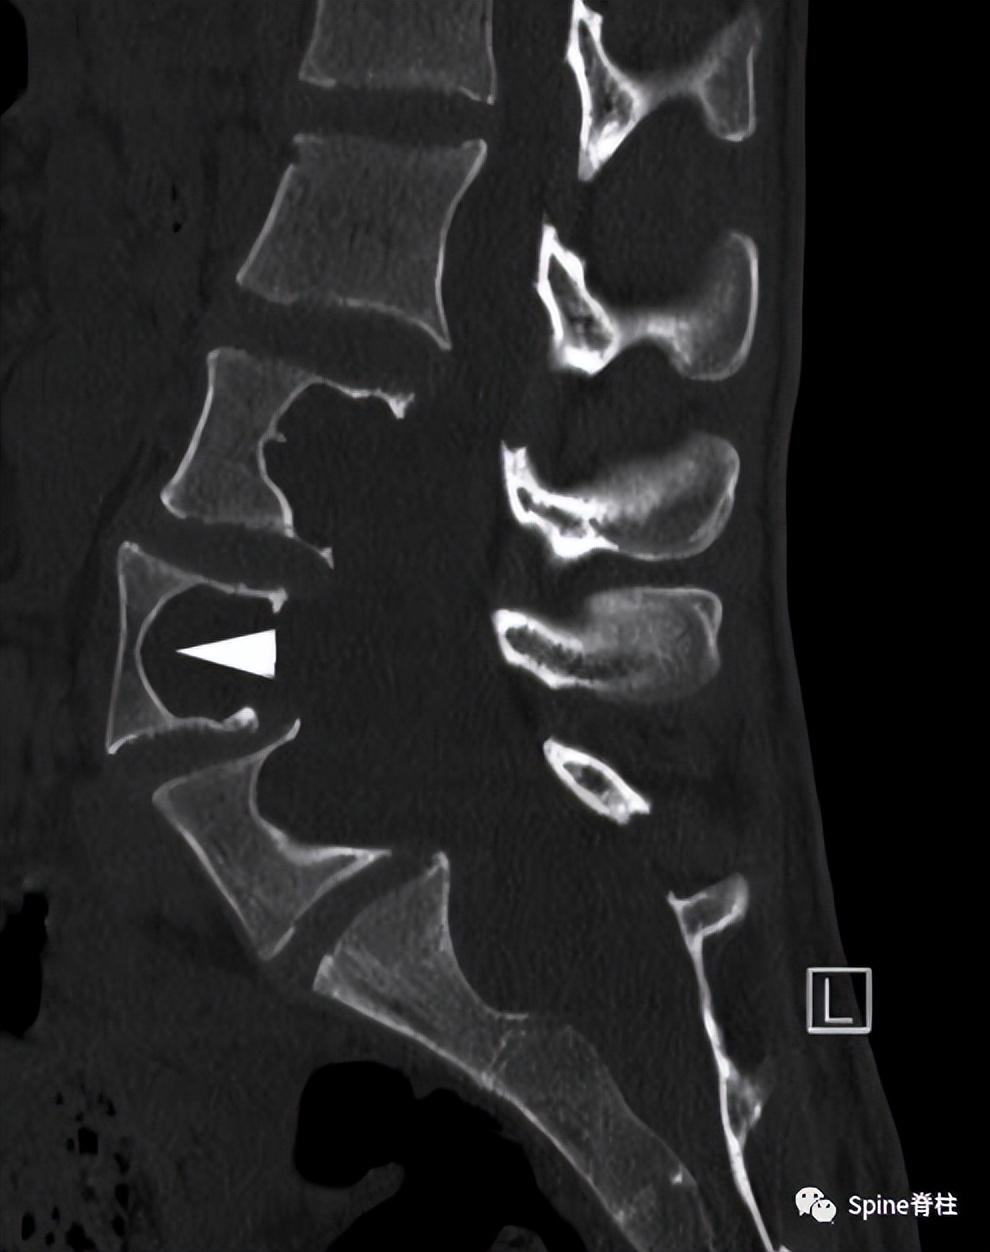

一名20 岁男性1型神经纤维瘤病患者出现背痛和下肢感觉障碍,肌力正常。随后,他出现尿潴留,感觉平面下降至 T10 水平。影像学提示硬膜扩张伴椎体后壁扇形缺损(箭头),L4/5轻度向前滑脱。CT横断面提示腰椎椎弓根拉长变细,双侧椎弓根骨折(箭头)。骨折在 MRI 上显示无水肿信号,提示为慢性骨不连骨折 PMID: 22232056